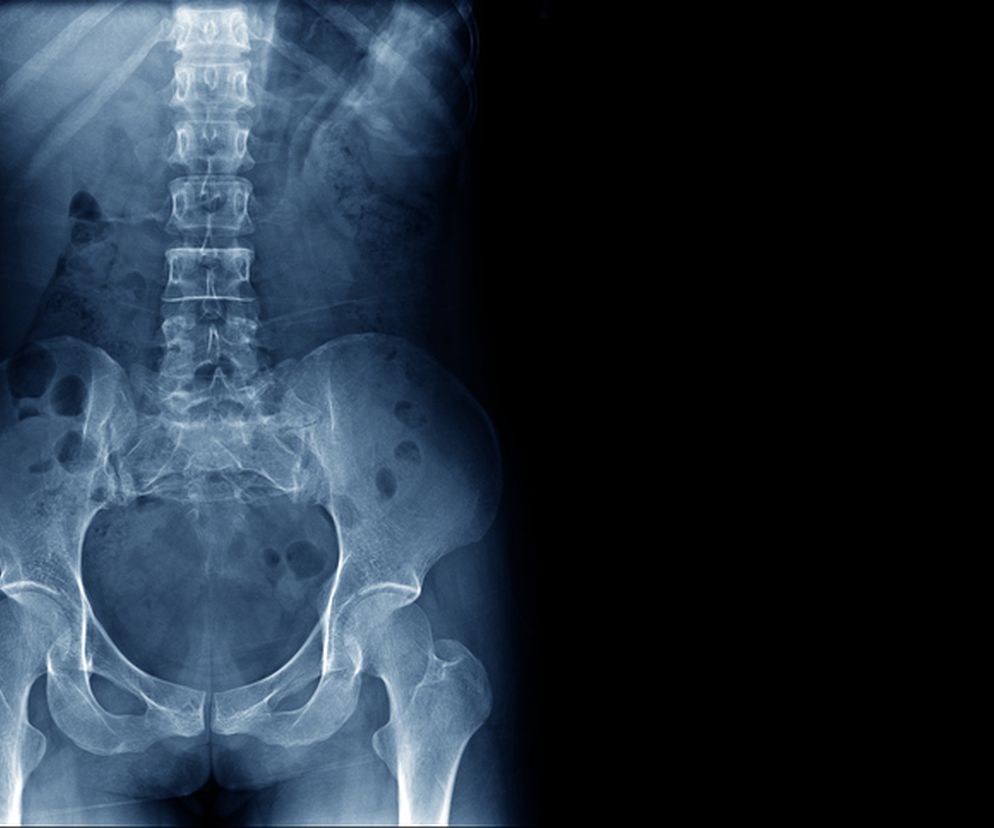

Spojenie łonowe

i

Autor: Getty Images